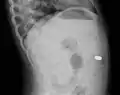

A coin seen on AP CXR in the esophagus

A coin seen on lateral CXR in the esophagus